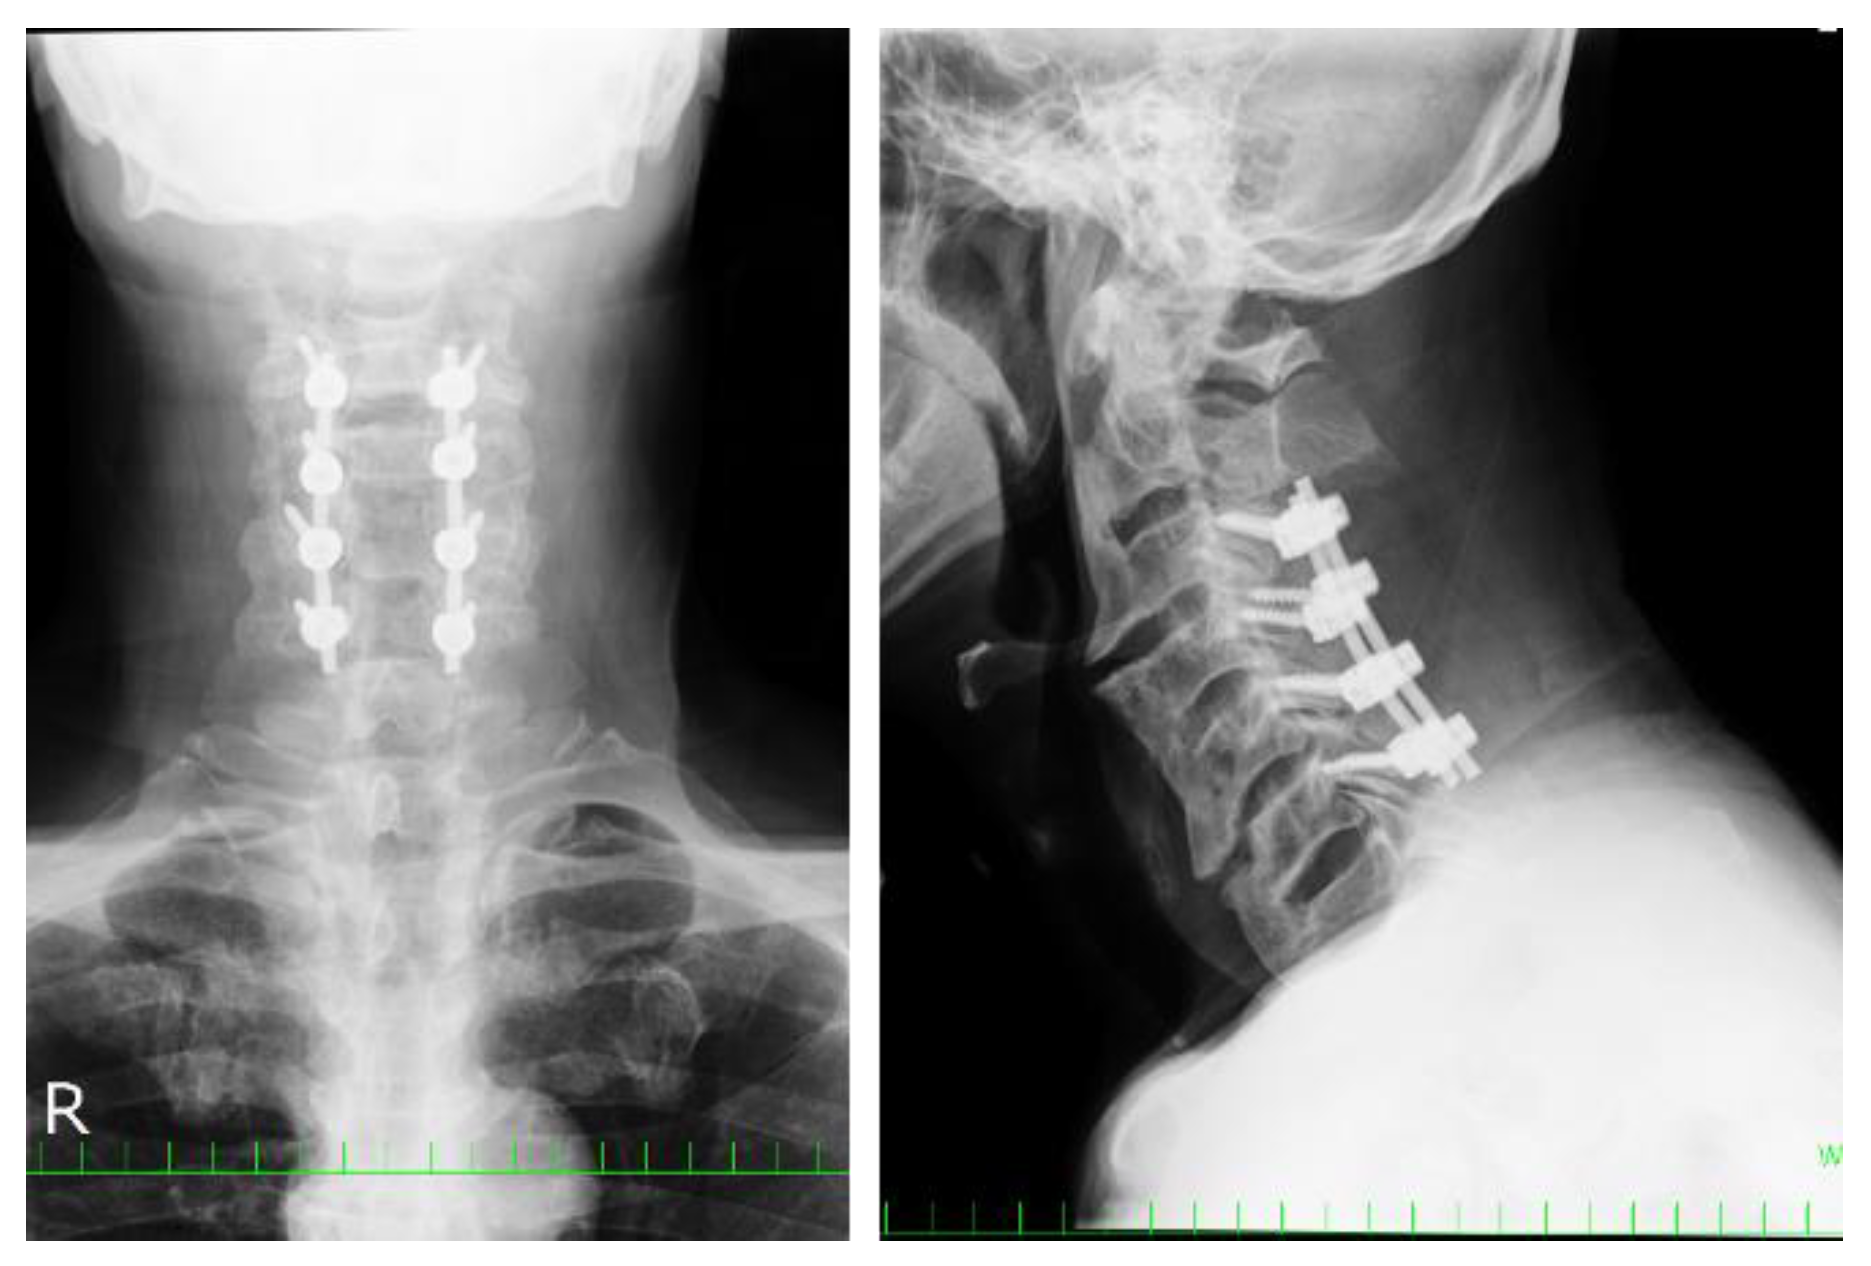

Ossification of the Anterior Longitudinal Ligament with Dysphagia as the First Symptom: Rehabilitation of Two Cases

2.5. Clinical Presentations